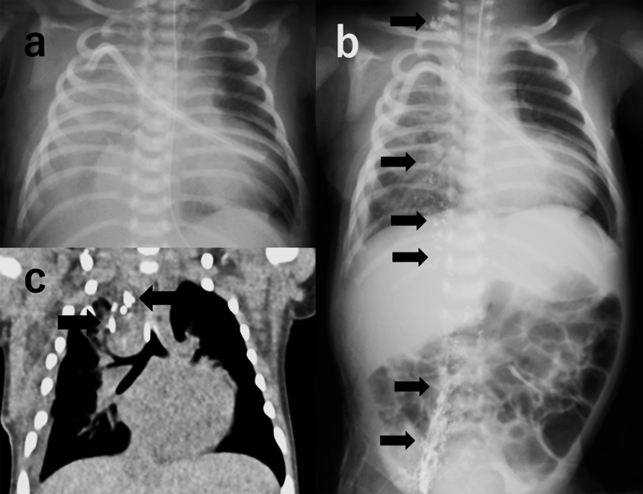

先天性心疾患術後難治性乳び胸に対してリピオドールリンパ管造影が有効であった新生児の一例Successful Intranodal Lymphangiography for Refractory Chylothorax in a Neonate with Congenital Heart Disease